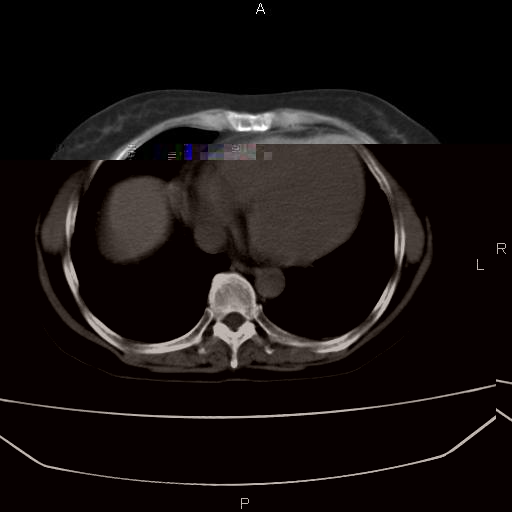

患者,女,66岁。健康体检胸部透视发现右上肺片状阴影。既往无不适,患者自诉三个月前曾有低热病史体温37.5左右一周。用药后缓解。至今无其它不适。请老师们指导指导。

考虑:右肺上叶周围型肺癌(分叶状肿块+砂粒状钙化+胸膜尾征)。

病灶见明显分叶、大小较大(大于3cm?),老年人,多考虑:肺癌,建议穿刺活检。

周围性肺癌,

右肺上叶周围型肺癌可能性大。

考虑:右肺上叶周围型肺癌